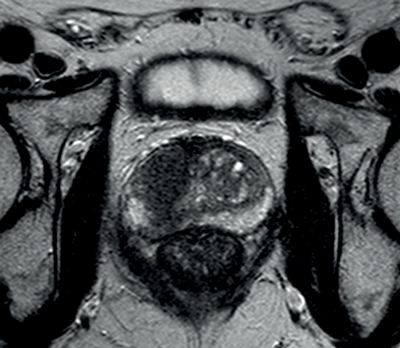

Figure 2a: Axial T2WI with low signal in the right central zone.

Figures 2b and 2c: DWI and ADC map confirm restricted diffusion at the site of tumour.

In prostate cancer, DCE MR follows the characteristic pattern of malignant enhancement with early, intense enhancement and rapid wash-out. It is most often correlated with T2-weighted and diffusion-weighted sequences for greater accuracy in detection (Figure 3).

Figure 3a: DCE image of the same patient as Figure 2 showing

avid enhancement in the right central zone tumour.